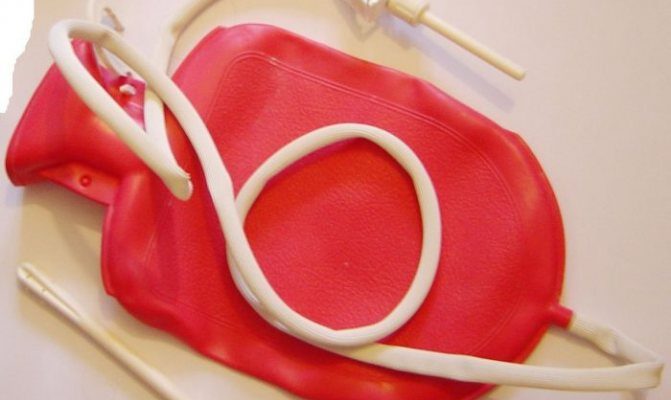

Як зробити розчин для клізми: Досвід, практичність та інструкції Коли ми говоримо про таку делікатну тему, як зробити розчин для клізми, часто виникає